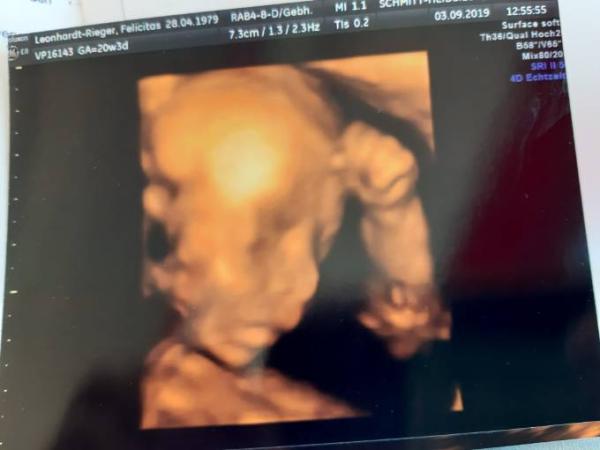

So, meine Lieben, die kleine Lady und ich haben den Termin heute zur Feindiagnostik super gemeistert. Der Arzt ist mit allen Untersichungsergebnissen total zufrieden. Die Organd sind alle super in Ordnung und die Versorgung könnte auch nicht besser sein. Mittlerweile misst sie schon 24cm und wiegt 360 Gramm. Und es bleibt bei Team rosa. Obwohl ich die 3D Bilder irgendwie gruselig finde, möchte ich es euch doch nicht vorenthalten. Hoffe, es geht euch allen so gut wie mir

Bild zu Pränataldiagnostik - Forum für Januar - Mamis